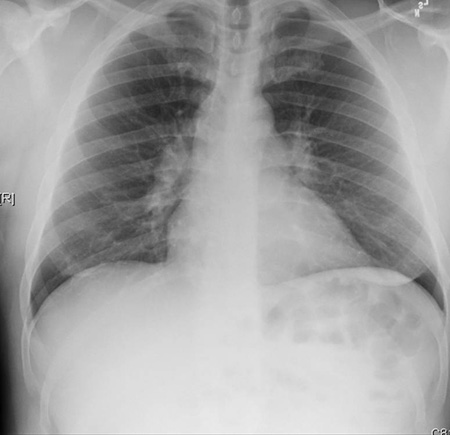

A. Portable upright chest x-ray before aspiration; B. Chest x-ray 1 hour after aspiration, showing bilateral diffuse alveolar infiltrates, worse at the bases on the right side

From the personal collection of Dr S. Murgu and Dr H. Colt, University of California at Irvine Medical Center